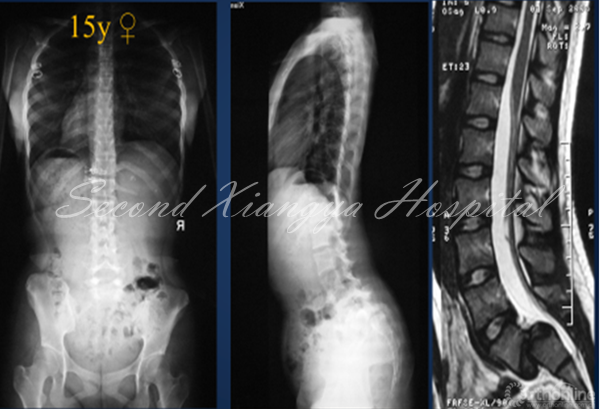

腰椎重度滑脱症定义是指椎体滑移率>50%,Meyerding>II度。青少年人群中发病率为2.4%,常累及L5/S1节段。发育,创伤,手术和病理是造成腰椎重度滑脱症的因素。依据SDSG分类,重度滑脱分为骨盆平衡,骨盆后倾和失平衡三种类型。从自然史讲,生长发育期间的腰椎重度滑脱症会出现进展,造成临床症状和脊柱矢状面失平衡,因而需要外科干预。

外科治疗腰椎重度滑脱症具有挑战性,如选择不当,往往会造成并发症,影响临床疗效和患儿日常生活。因此,笔者结合文献和自身经验,浅谈一下如何合理选择矫正方案以降低并发症。

1. 骶骨形态重度不良

对重度骶骨发育不良者,先天遗传是主要原因。2015年,罗卓荆团队通过两个家系[6],鉴定了2个新型错义突变,功能研究显示软骨发育过程中,磷酸化摄入障碍是其发病主要的分子机制。遗传因素造成的骶骨穹窿形态不良,通常较为严重,并会造成L5椎体梯形变,导致滑脱进展,并使得外科治疗此类畸形较为困难。

2. 骶骨形态不规则

骶骨形态不规则,通常是由于力学因素造成的。2012年,Sevrain[7]根据PI值将滑脱分为低PI组和高PI组,生物力学测试结果表明,低PI组人体重心位于骶骨中后区,而高PI组重心则分布在骶骨前方。从而更容易造成骶骨形态发生轻度或中度形态变化,L5椎体出现相应梯形变,从而亦会造成滑脱进展。

• 青少年腰椎重度滑脱有进展风险

• 手术方式包括原位融合、部分复位或完全复位等

• 骶骨严重发育不良、腰椎前凸过大、矢状面失平衡,以及植骨方式不当是手术失败主要原因

• 具体手术方式应根据矢状面平衡状况和骶骨形态合理选择,以减少并发症发生.